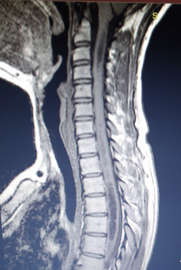

Εικόνες 20.1.α. & 20.1.β. Προεγχειρητικές μαγνητικές τομογραφίες δείχνουν την κάθοδο (κήλη) των αμυγδαλών της παρεγκεφαλίδος δια μέσου του ινιακού τρήματος και την πίεση που ασκείται στο εγκεφαλικό στέλεχος (20.1.α.) και στον αυχενικό και θωρακικό νωτιαίο μυελό από την σύριγγα (20.1.β.).

Η μαγνητική τομογραφία της κρανιοαυχενικής συμβολής έδειξε ότι η ασθενής έπασχε από Σύνδρομο Chiari σε συνδυασμό με Συριγγομυελία, και από κάθοδο (κήλη) των αμυγδαλών της παρεγκεφαλίδος, πίεση του νωταίου μυελού και ανάπτυξη σύριγγας, δηλ. επιμήκους κοιλότητας με υγρό στην αυχενική και θωρακική περιοχή του νωτιαίου μυελού. Σε τέτοιες περιπτώσεις, η σύριγγα δρά πιεστικά στο νωτιαίο μυελό και αυτό προκαλεί τα νευρολογικά προβλήματα.